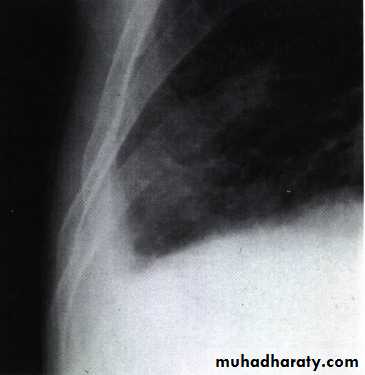

Chest X ray: The pleural fluid accumulates in the most dependent part of the thoracic cavity

The normally sharp posterior costophrenic angle is obliterated.

Upper surface is meniscus-shaped (meniscus sign).

Around 200 mL of fluid is required in order for it to be detectable

on a PA chest X-ray

The amount of pleural effusion may be small, large or massive.